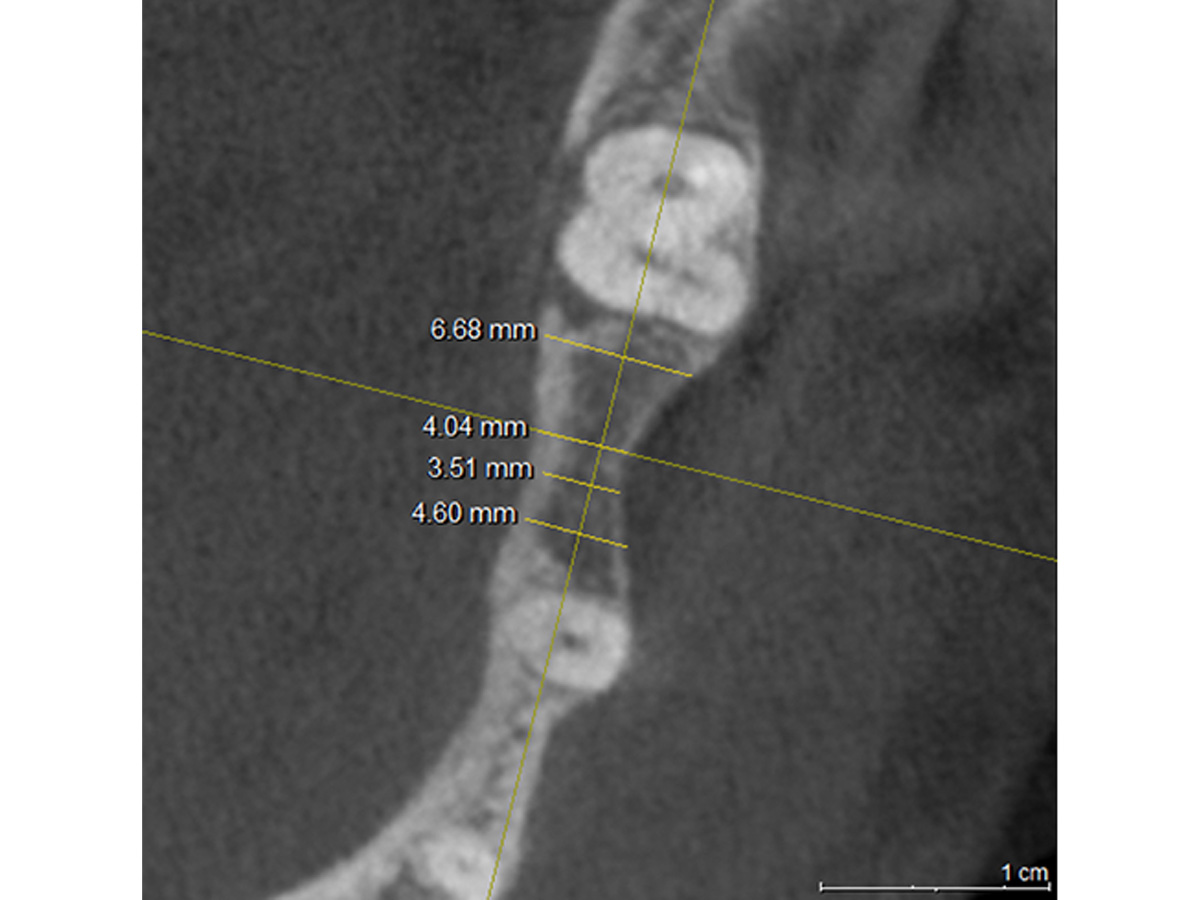

Einen horizontalen Schnitt durch die entsprechende Knochenregion mit den gemessenen Knochenbreiten zeigt Abb. 3, während Abb. 4 die geplante Implantatgröße mit den Knochenbreiten im zervikalen Anteil des Kieferkammes abbildet.

Horizontaler Schnitt durch die entsprechende Knochenregion und gemessene Knochenbreiten.

Abbildung 3